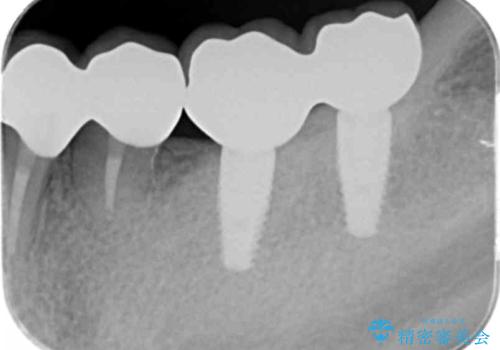

銀歯を外し、インプラントを入れたい

- 「治療途中の歯を治したい。この際、銀歯も全て外したい。インプラントも入れてしっかり噛めるようにしたい。徹底的に歯の治療をしたい。」

と総合的な治療を希望され来院されました。

ここの歯の状態を精密に検査し、根管治療、セラミック治療、インプラント治療を含む総合的な歯科治療を計画します。

- 242万円(ジルコニアクラウン・仮歯×7本 インプラント×2本)費用は治療当時の料金となります

部分的な治療ではなく、全体的な治療を任せていただけたことで、清掃性の高く咬合関係の良い治療を行うことができました。

見た目の改善だけでなく、噛み合わせの仕上がりにも大変満足いただくことができました。